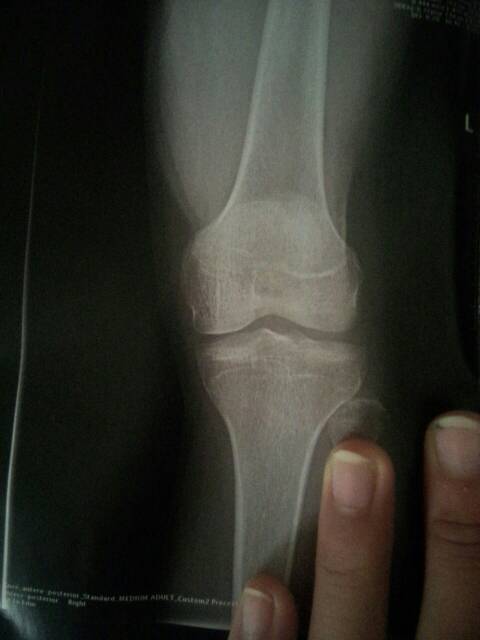

2、X光檢查:X光檢查是判斷骨骺線是否閉合的最準(zhǔn)確方法,通過拍攝手腕或膝關(guān)節(jié)的X光片,可以清晰地觀察到骨骺線的狀況,如果X光片中顯示骨骺線已經(jīng)消失,說明骨骺線已經(jīng)閉合。